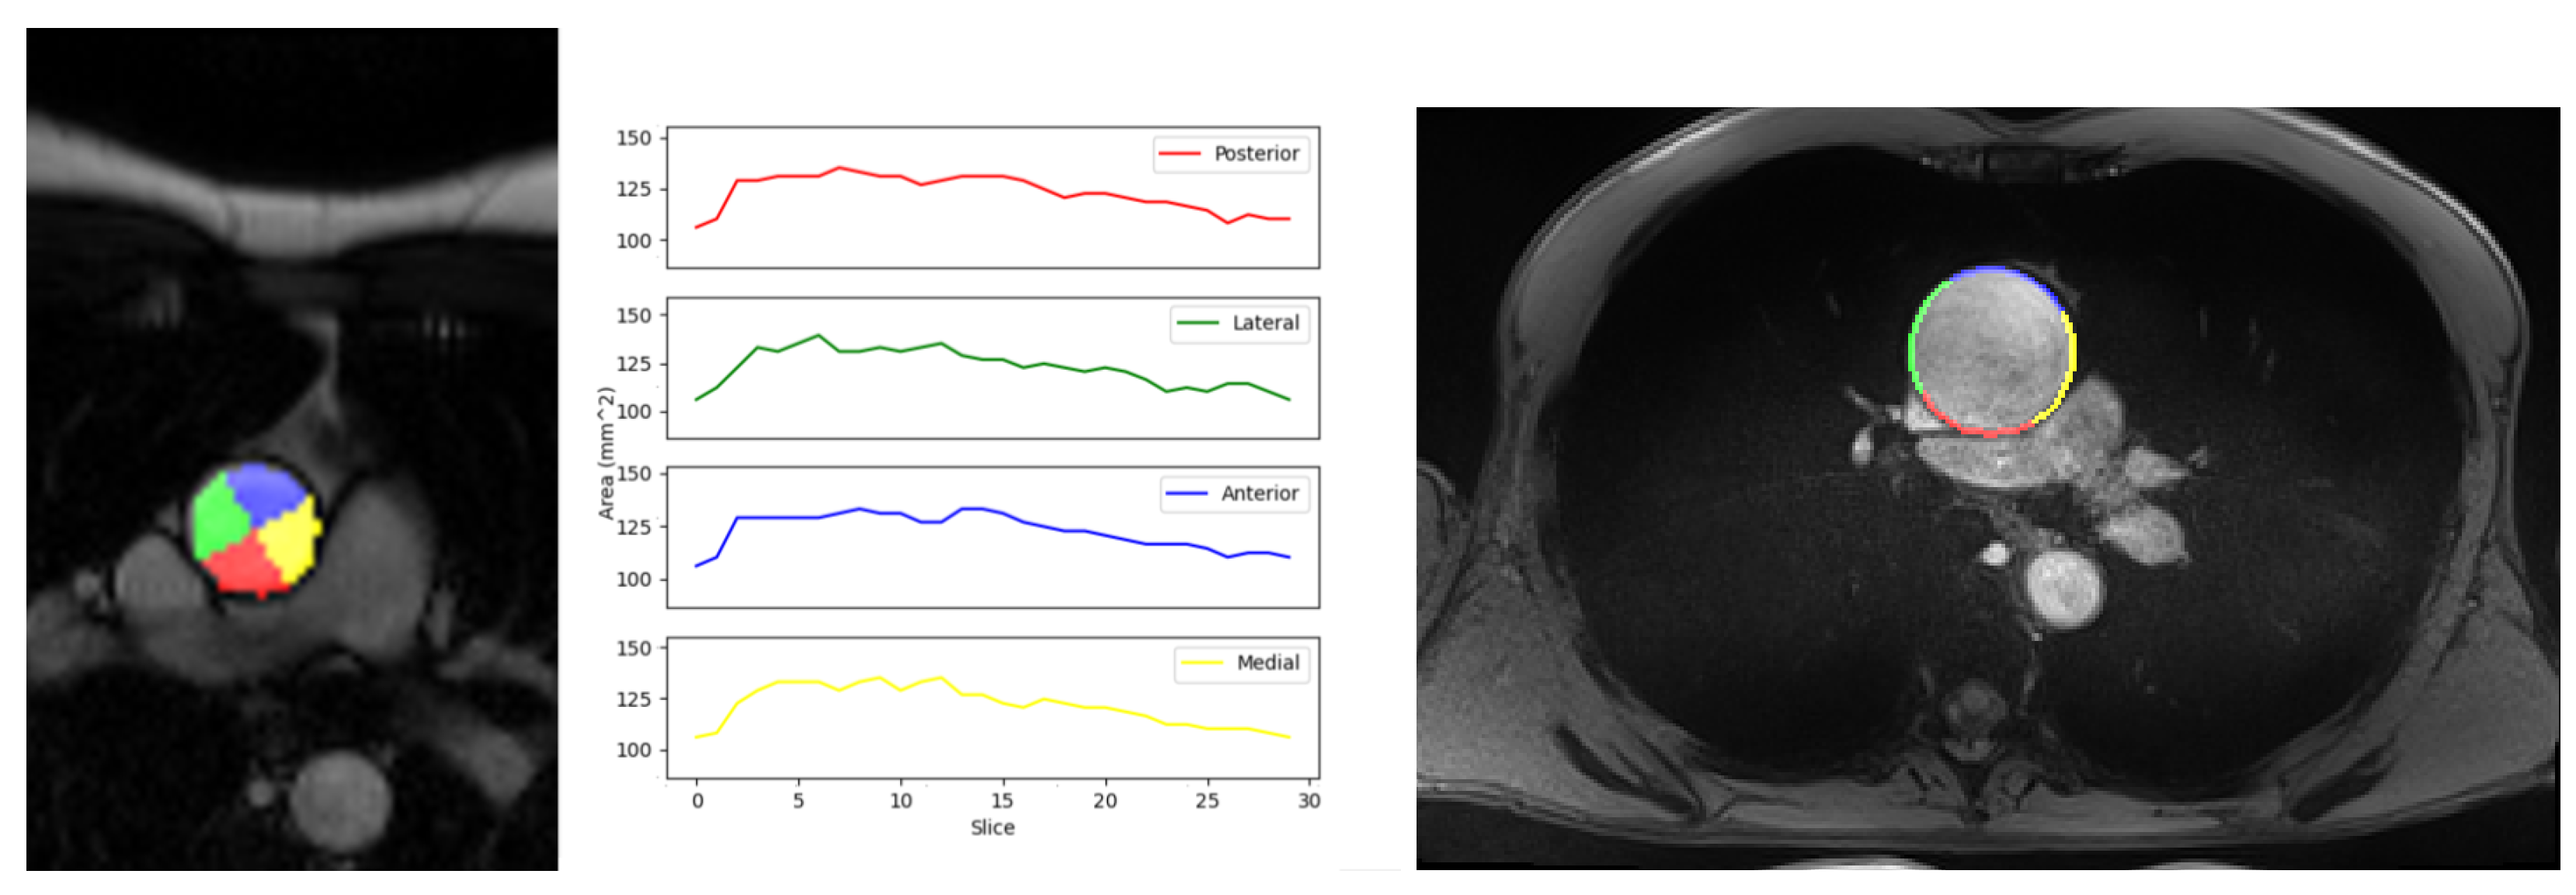

3.3. Local Elastic Properties’ Evaluation

| Quadrants | Medial | Anterior | Lateral | Posterior |

|---|---|---|---|---|

| Compliance Mean ± Std. Dev. (mm/mmHg) | 0.511 (±0.25) | 0.462 (±0.19) | 0.534 (±0.21) | 0.491 (±0.18) |

| In-vivo Strain Mean ± Std. Dev. | 0.086 (±0.03) | 0.072 (±0.02) | 0.097 (±0.03) | 0.095 (±0.04) |

| Maximum Young’s Modulus Mean ± Std. Dev. (MPa) [9] | 0.622 (±0.19) | 0.768 (±0.24) | 1.208 (±0.47) | 0.993 (±0.31) |

| Physiological Young’s Modulus Mean ± Std. Dev. (MPa) | 0.354 (±0.13) | 0.362 (±0.15) | 0.411 (±0.13) | 0.419 (±0.15) |